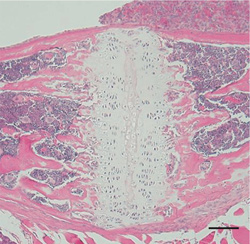

Figure 3: Image of mouse norma sagittalis, spheno-occipital synchondrosis portion

Left: BALB/c mouse, right: BALB/c-bm/bm mouse. Obvious difference in formation of cartilage.

Figure 4: Image of mouse norma frontalis, septal cartilage

Left: BALB/c mouse, right: BALB/c-bm/bm